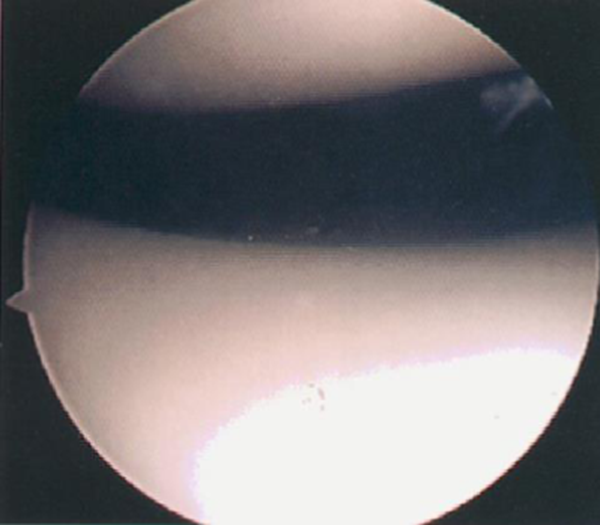

关节镜下髌骨软化症0级表现

0级:正常关节软骨